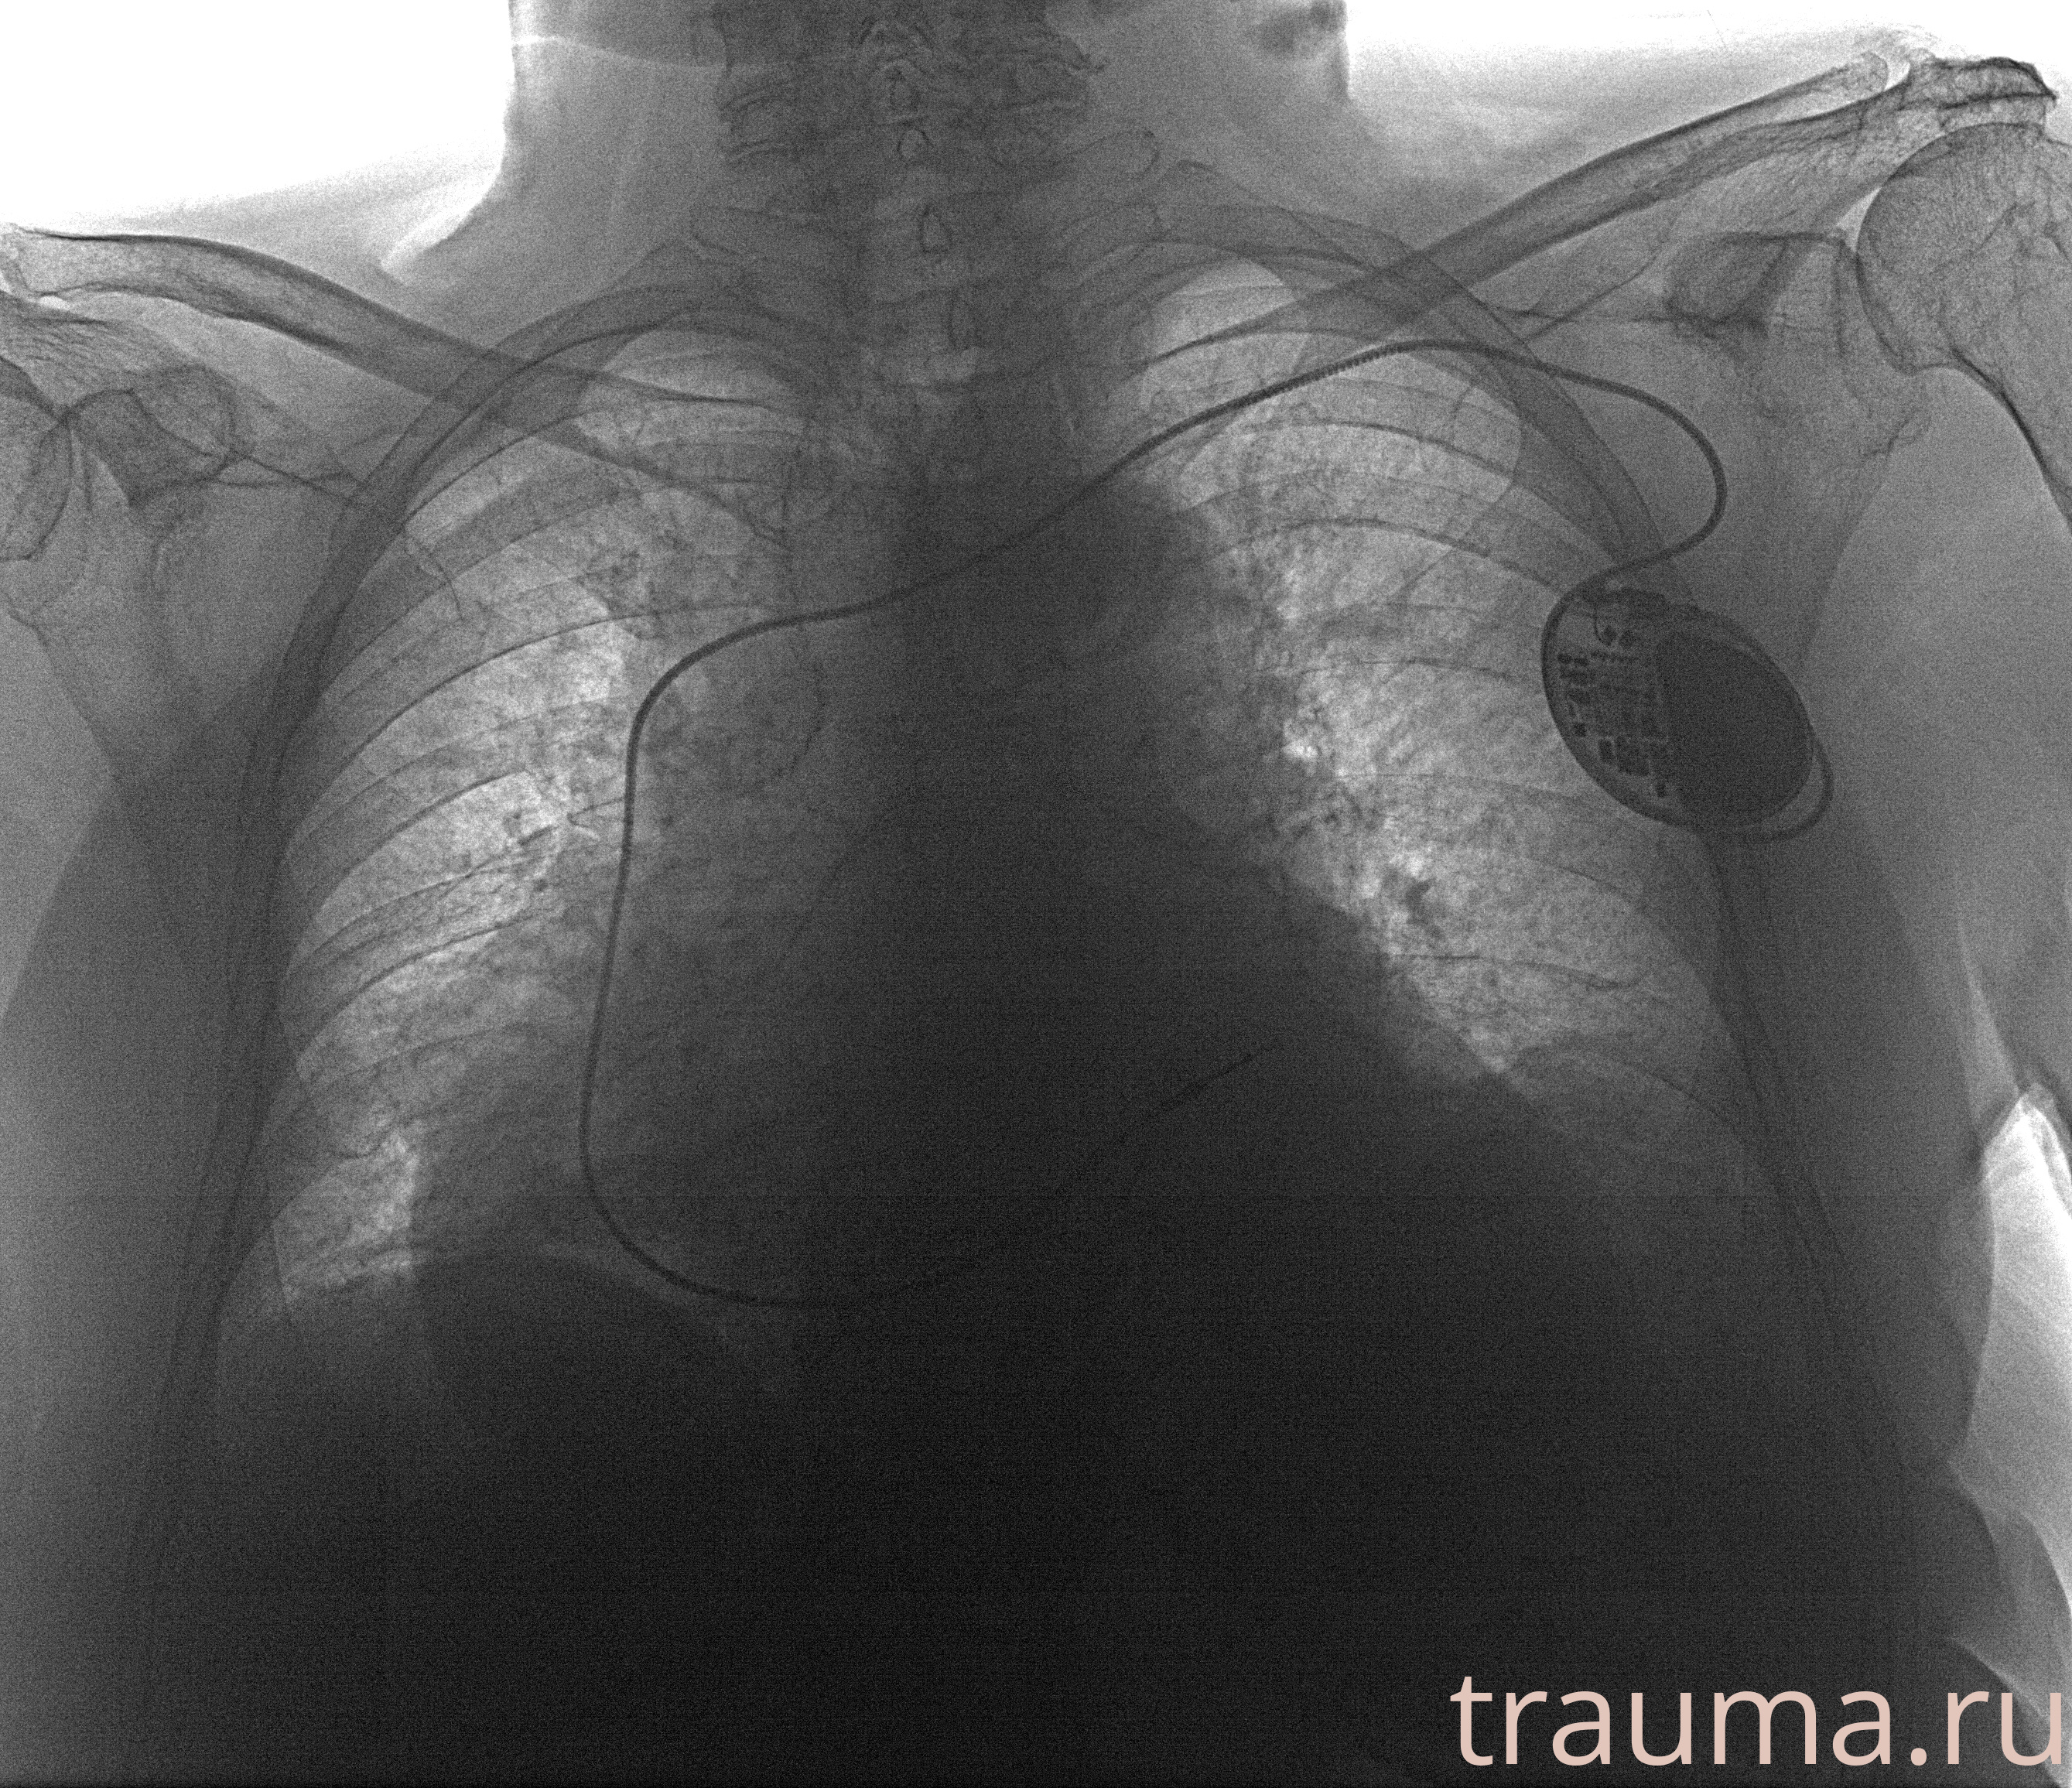

Рентгенограммы

Рентген на дому: по вашему адресу приезжает врач-рентгенолог, травматолог-ортопед с мобильным рентгеновским аппаратом, проводит диагностику травмы или заболевания, делает необходимые рентгенограммы, дает рекомендации по дальнейшему лечению. Получить качественные снимки в домашних условиях возможно благодаря уникальной методике, разработанной МосРентген Центром для института  Склифосовского